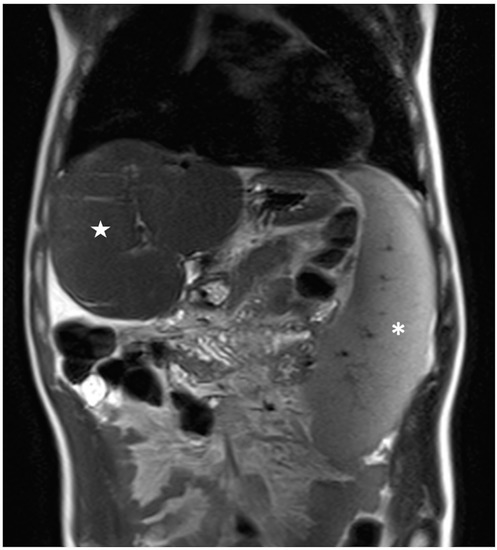

3.2. Magnetic Resonance Imaging